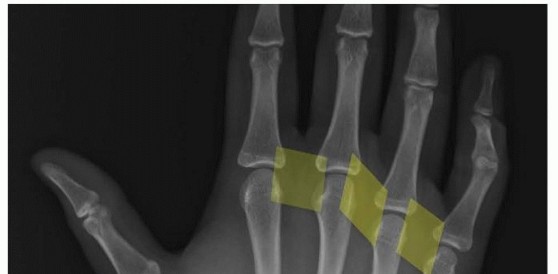

14 MIN READ Operative Treatment of Finger Carpometacarpal Joint Fracture-Dislocations يناير 2023 Read More